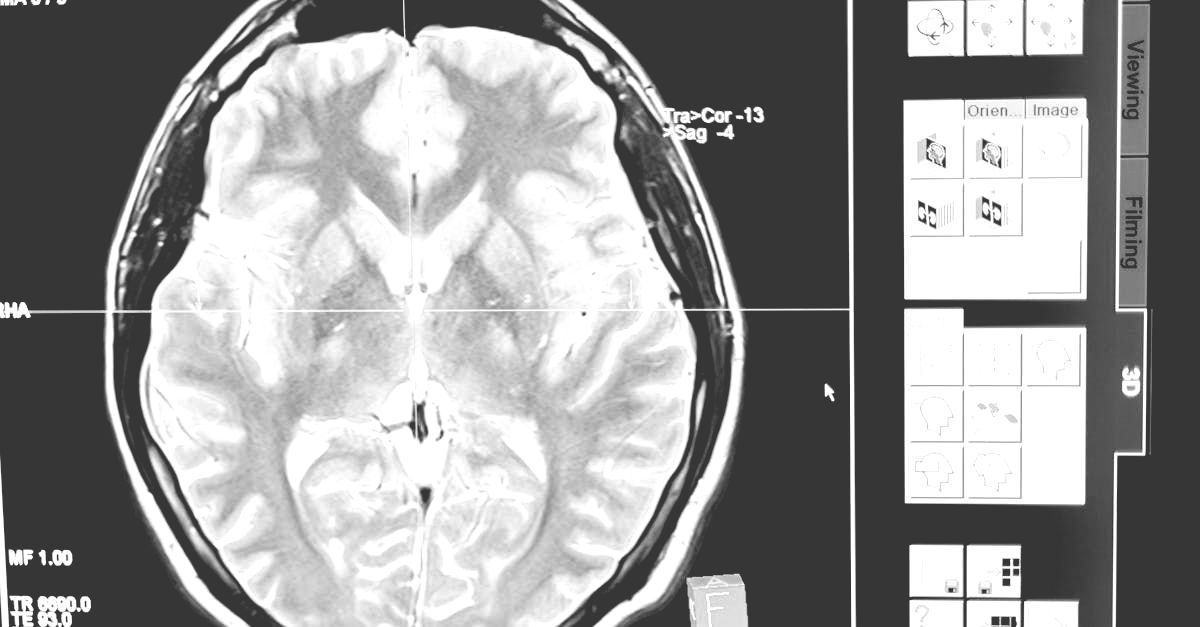

In August 2020, Thriftmaster partnered with Augusta University and Dr. Babak Baban to explore the therapeutic potential of our proprietary CBD blend and Metered Dose Inhaler delivery system. TGB provides the university funding, product formulation and research support, resulting in exclusive rights to the intellectual property created by Dr. Baban's research. This collaboration has led to the publication of six peer-reviewed papers focused on TGB’s inhaled CBD blend and delivery system as a therapy for severe conditions. Many additional studies are in progress. Dr. Baban is preparing to initiate human clinical trials for these conditions (Glioblastoma and Alzheimer's therapy) pending FDA approval.

TGB actively broadens our pre-clinical testing initiatives to assess the therapeutic potential of our products across a diverse spectrum of conditions, with primary focus on the brain, lungs and central nervous/inflammatory system(s). Our unwavering commitment to rigorous research positions us at the forefront of innovative therapies in this theater of study.